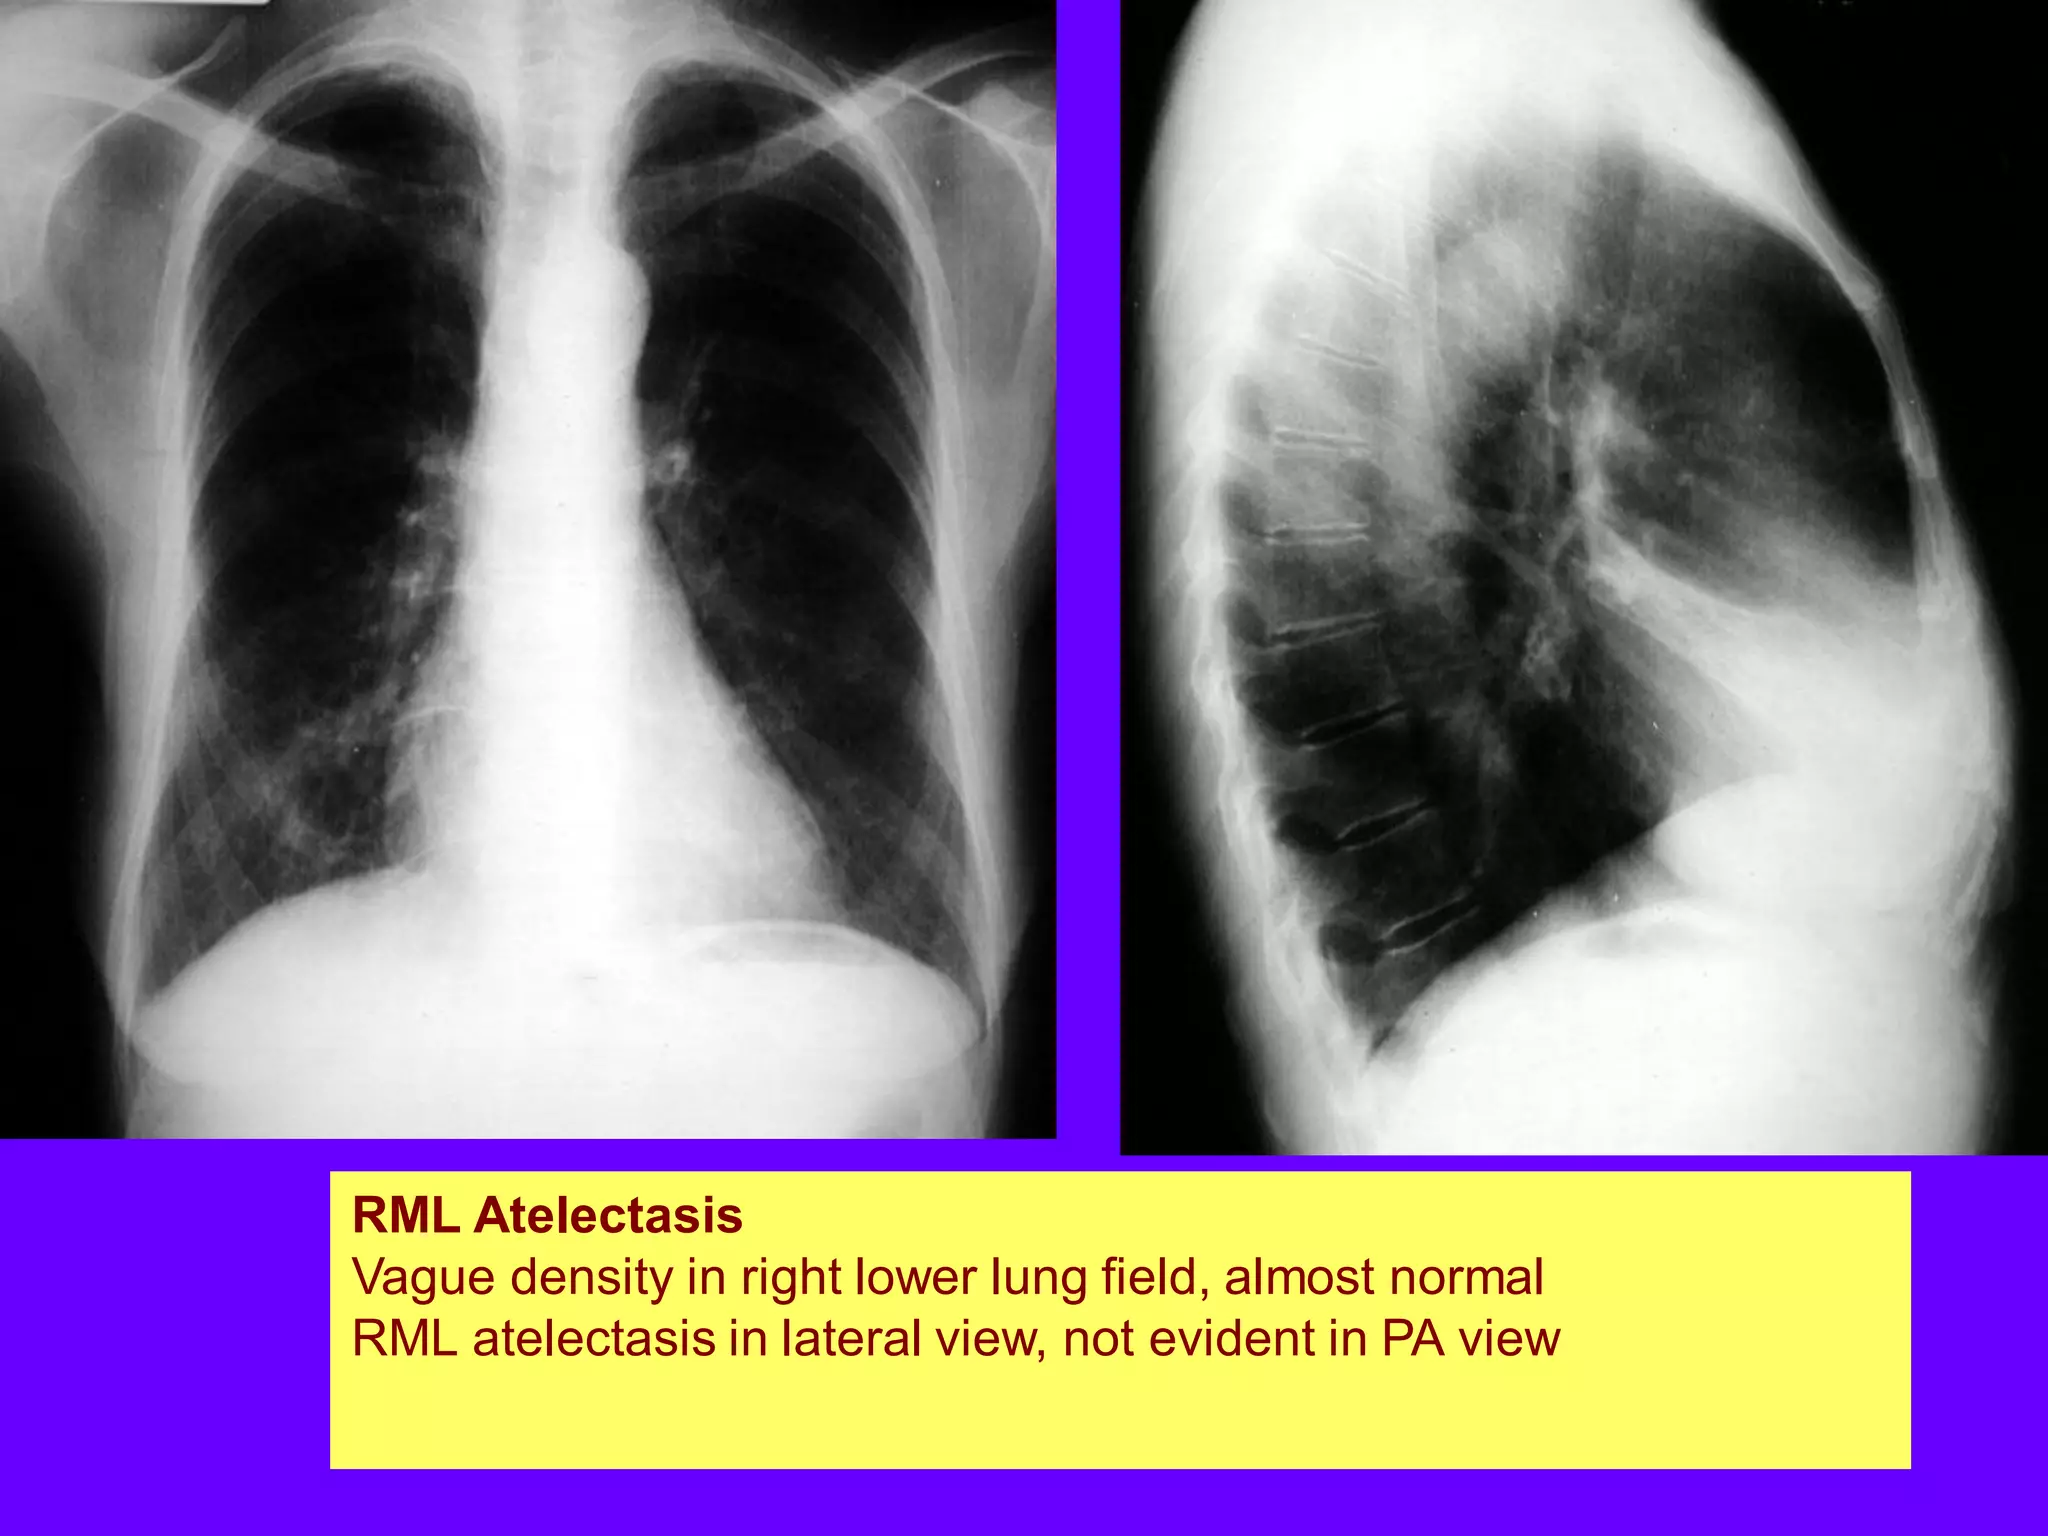

RML Atelectasis

Vague density in right lower lung field, almost normal

RML atelectasis in lateral view, not evident in PA view